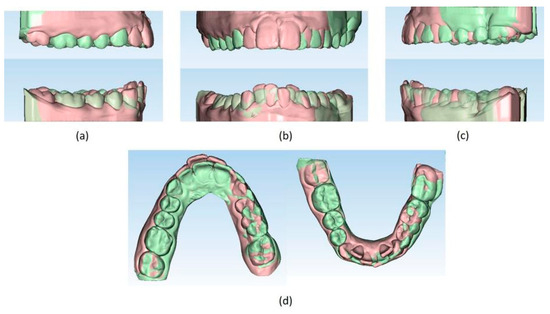

Figure 10.

(a–d) Superimposition of pre- (light orange) and post- (light green) treatment virtual models (Maestro 3D© software, Version 6, AGE Solutions S.r.l. Pontedera, Tuscany, Italy).

The setup indicated the need to treat the patient with 44 upper and 24 lower aligners, equal to 22 movements in the upper arch and 14 movements in the lower arch. The treatment required 10 months and 2 weeks. The Sorridi® system (Sorridi®, Sorridi s.r.l., Latina, Italy) used in this clinical case is a no-attachment system, which alternates weekly between two aligner thicknesses: soft (0.06 mm) and hard (0.08 mm), for each programmed movement. Soft aligners are used in the first week, then hard aligners are used for another week until the next soft-type aligner. The gingival margin is straight beyond the gingival zenith above 2 mm (Figure 5). No interproximal reduction (stripping) and divots to guide dental movements were required. No hybrid supports were programmed (corticotomies, mini-screws, elastics). No further refinements were deemed urgent. Orthodontic retainers were applied even if a slight mesio-lingual rotation of the second left lower molar orthodontically transposed in place of the missing first molar was present (Figure 6). Post-treatment radiographs were requested (Figure 7 and Figure 8) and new cephalometric analysis was performed (Table 3). The patient finished the treatment remaining in the skeletal class II from biretrusion (SNA 78.5°, SNB° 73.8°), but the unfavorable ratio between maxilla/mandible improved (ANB 4.8°). The long and hyperdivergent face pattern remained (OP-SNP 21.6°, FMA 27.5°). The mandibular inclination returned to normal values (MPGoGn-SNP 34°). Lower incisors’ inclination was corrected (1-NB 25.4°, IMPA 94.8°), upper incisors’ inclination strongly improved (1-NA 17.4°) and overjet and overbite were strongly reduced to values almost close to normal (both equal to 3 mm) (Figure 9). Pre- and post-treatment superimposition of virtual models allowed us to evaluate the extent of movements that were actually obtained (Figure 10). Furthermore, distances were measured on virtual models before and after the orthodontic treatment. The upper edentulous space (from the distal surface of the second premolar to the mesial surface of the second molar) initially measured 5.33 mm and 0.11 mm at the end of treatment, the lower one (distal to the second premolar and mesial to the second molar ipsilaterally) was 7.68 mm and it was closed completely, leaving just 0.9 mm. The distance between the cusp of the left upper canine and the disto-buccal cusp of the ipsilateral upper second molar was 29.88 mm, and then decreased to 24.33 mm with a variation in the upper intercanine distance of just 1.64 mm (from 28.31 to 29.95 mm). It indicates that much of the closure was due to mesialization of the molar as well as distalization of the lateral teeth. In the lower arch, the distance between the cusp of the left canine and the disto-vestibular cusp of the second molar decreased, going from 30.42 mm to 24.59 mm, almost 6 mm, with a variation in the intercanine distance from the initial 20.36 mm to 23.73 mm. The resolution of anterior crowding and a reciprocal movement of distalization of the canine-premolar sector and mesialization of the second molar, all equal to about half a cusp each, led to an optimal closure of the posterior edentulous space.